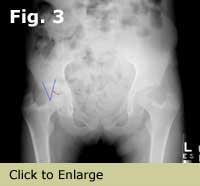

AP pelvis showing sourcil, sourcil angle, weight bearing axis, fovea and tear drop on the right hip, and posterior wall sign and cross over sign on the left hip

Figure 1. AP pelvis showing sourcil, sourcil angle, weight bearing axis, fovea and tear drop on the right hip, and posterior wall sign and cross over sign on the left hip.